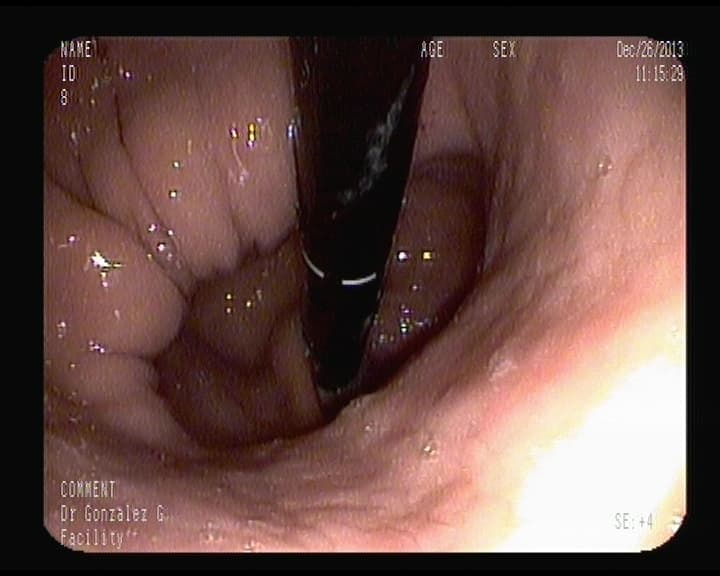

Hemorragia digestiva alta.

Punto sangrante en Duodeno, solucionado con colocación de un clips metálico,